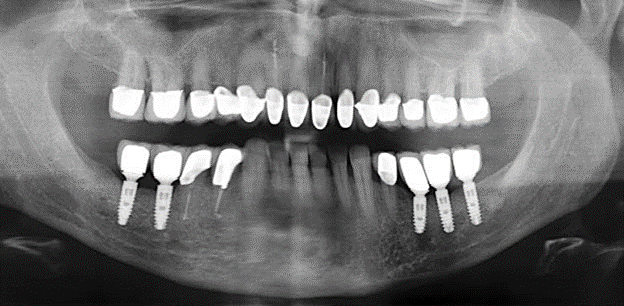

Fig. 3: Panoramic radiograph after ten years with implants.

The ten-year check-up revealed no indications of advancing clinical attachment loss or peri-implant bone substance loss (Fig. 3).